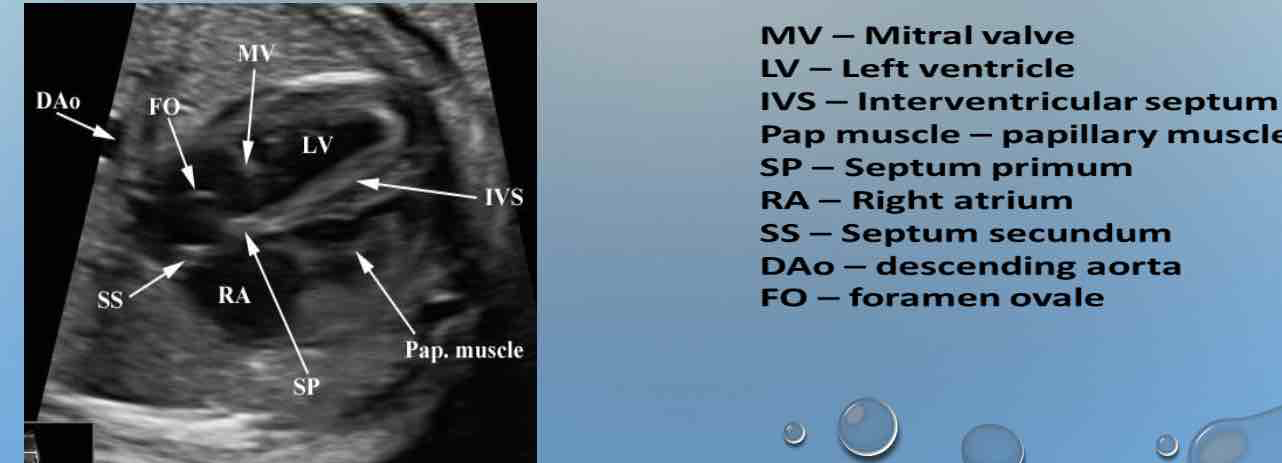

IMAGE 2:

4 CHAMBER HEART

4CH HEART

what plane?

what level?

each side…

types?

NORMAL FOUR-CHAMBER VIEW

• TRANSVERSE PLANE OF THE CHEST

• LEVEL OF THE FOURTH RIB

• ONE COMPLETE RIB ON EACH SIDE OF LATERAL CHEST

WALL

• TYPES - APICAL; SUBCOSTAL

two atria (characteristics)

Two ventricles (characteristics)

Equal size

Morphologic LA and RA

Flap of foramen ovale in LA

Atrio-ventricular concordance

Two ventricles:

Equal in size and contractility

Morphologic LV and RV

Moderator band (MB) in RV